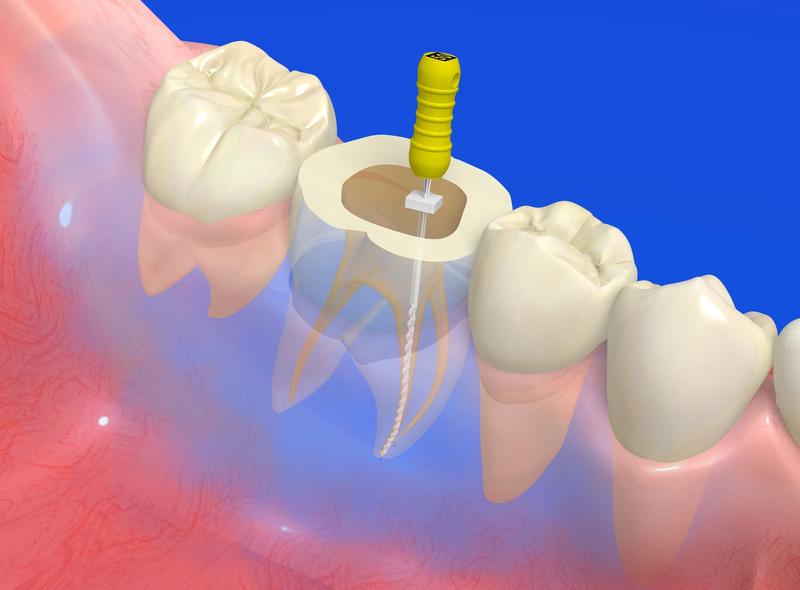

⻭の中⼼部には「根管(こんかん)」という細い管があり、その中には神経や⾎管(⻭髄)が通っています。

⾍⻭が進⾏して細菌がこの根管まで到達すると、激しい痛みや腫れを引き起こします。

⻭内療法では、この汚染された神経や細菌を専⽤の器具で徹底的に取り除き、管の内部を洗浄・消毒します。

内部が完全に清潔になったことを確認した上で、再び細菌が⼊り込まないよう隙間なく詰め物をして密閉します。

いわば、歯の内部をリフォームして「細菌を極限まで取り除く」精密な治療なのです。